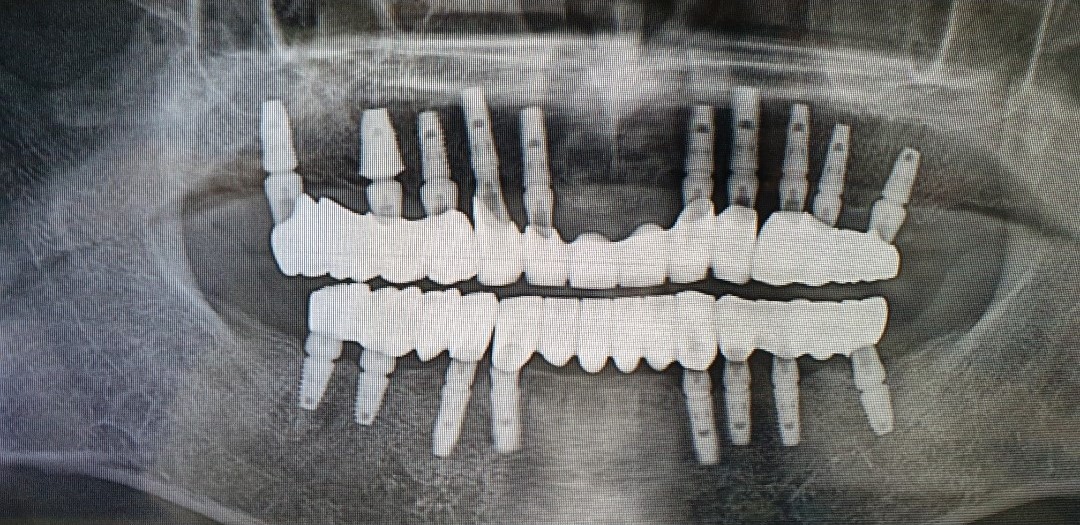

| 이플란트치과의원 | 천곡동 삼양골든빌딩 3층 | 임플란트, 틀니 전문 | 평일 09:30~18:00 (토/일 휴무) | 상담 권장 |